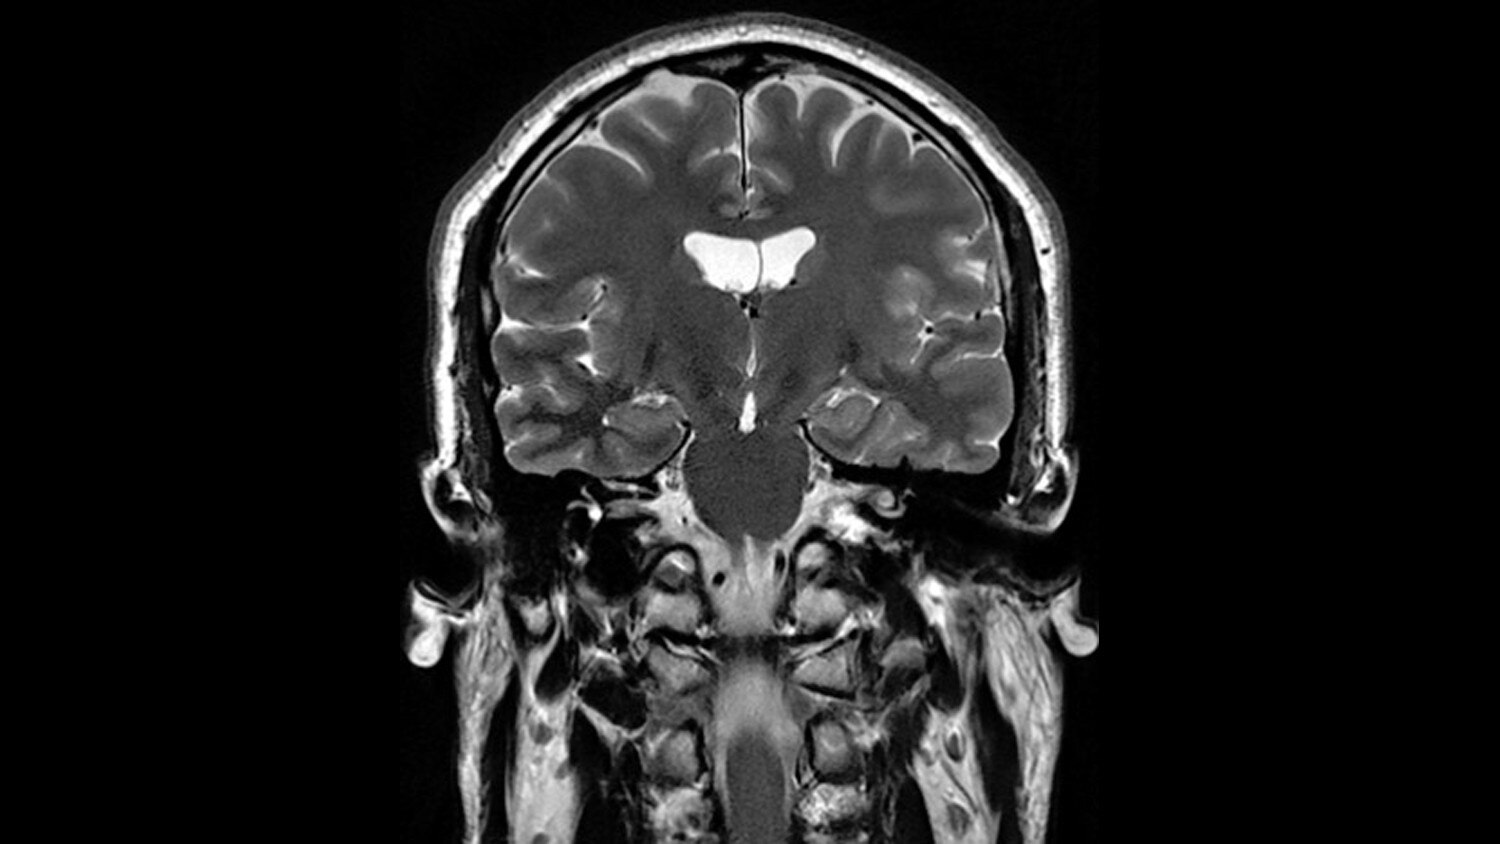

• MAGiC (Magnetic Resonance Image Compilation)

Click here to discover the MAGiC Experience

For the first time ever in the industry, you can generate multiple image contrasts in a single MRI scan including T1, T2, STIR, T1 FLAIR, T2 FLAIR* and PD contrasts of the brain in a single acquisition.

One scan that can do the work of many, with images acquired in as little as half the time to acquire separate sequences, fully integrated in a seamless workflow.

*It is recommended to acquire conventional T2 FLAIR images in addition to MAGiC.

• MAGiC

Complete flexibility for multiple contrast changes

You can change the contrast of the image by manipulating TR, TE and TI even after the scan is completed and the patient has exited the MR room. MAGiC processing will provide you any desired contrast paving the way to new diagnostic capabilities.

MAGiC even goes beyond standard MR weighted images by processing raw data into parametric T1, T2 and PD maps.